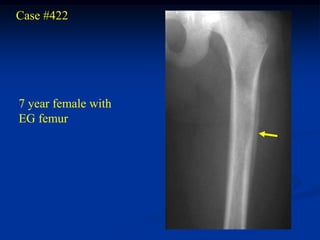

Case #422

7 year female with

EG femur